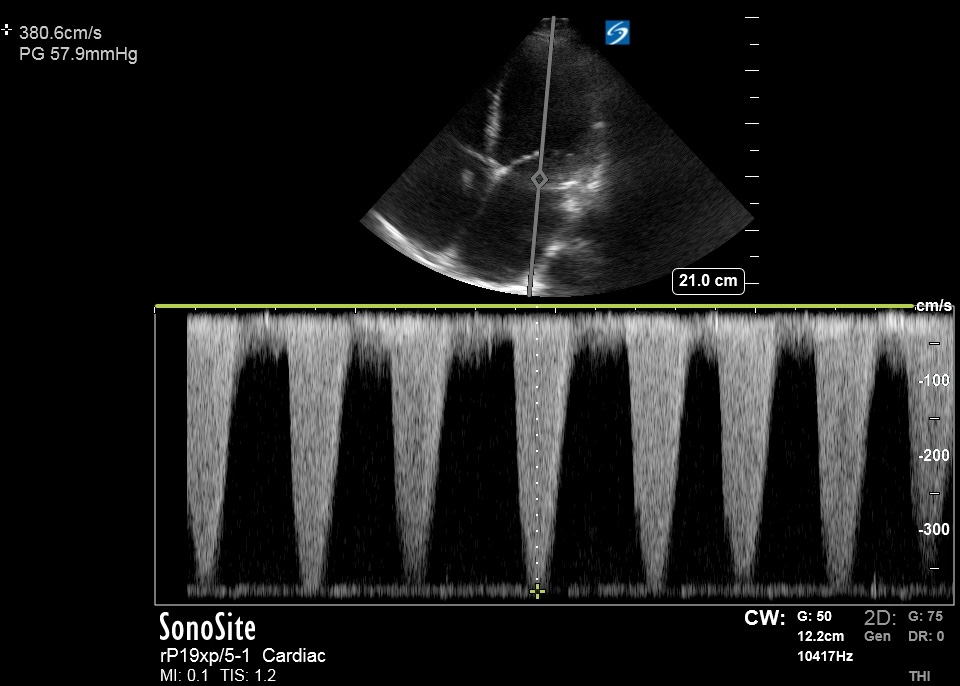

Bedside US done ~2 hours prior to RHC:

Bedside US done ~2 hours prior to RHC:

SVR estimated based on MRVmax/LVOT VTI ratio. (3.8/8.48) = 0.45

(>0.27 correlates with > 1120 dynes per onlinejase.com)

(>0.27 correlates with > 1120 dynes per onlinejase.com)